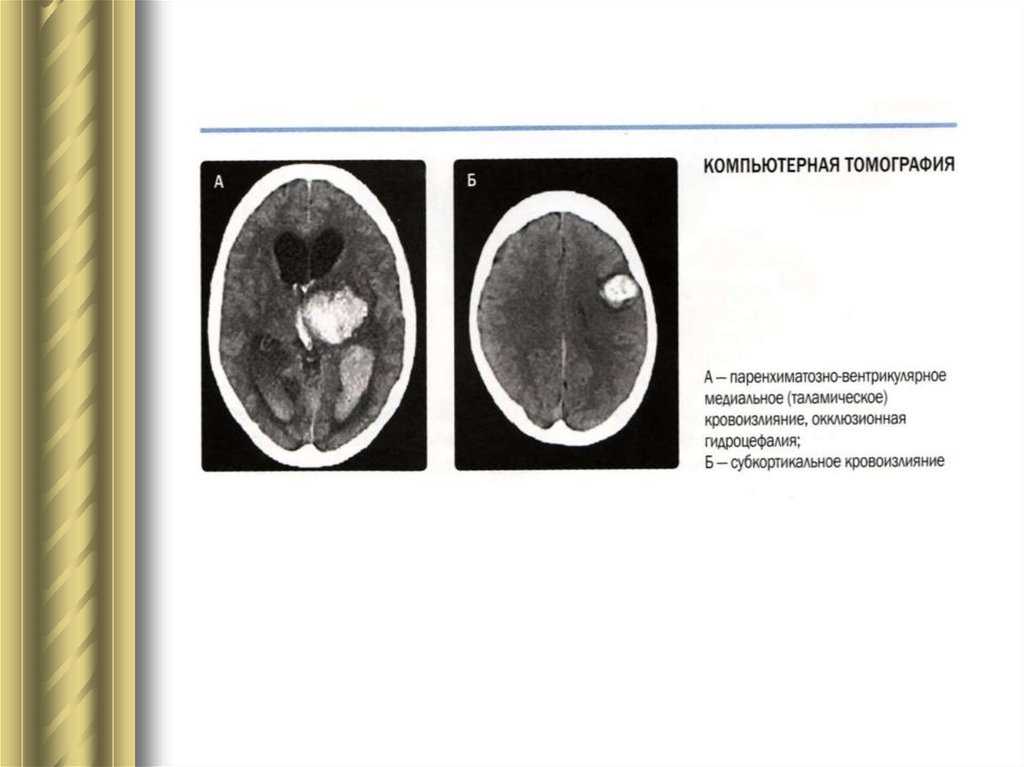

Геморрагический инсульт:

- Внутримозговые (паренхиматозные)

кровоизлияния.

- Субарахноидальные кровоизлияния.

Геморрагический инсульт – кровоизлияние в мозг, в

связи с разрывом сосуда или диапедезного

просачивания.